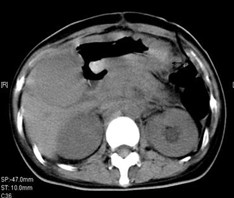

女,49岁。胃体癌晚期,胃窦增厚强化,与周围粘连,腹膜增厚,腹腔广泛转移,伴大量腹水。放/化疗失败,无法手术。治疗方案:腹腔灌注今又生2×1012VP/2次/周,共12周,同时灌注顺铂和5-氟尿嘧啶腹腔,后4周加8次全腹热疗。治疗后:第3周,腹水消失;第8周,胃窦、腹膜和网膜变薄,盆腔结节明显变小。后行手术切除残余胃肿瘤,术中探查全腹和盆腔未扪及肿瘤。术后病检胃肿瘤内未见癌细胞。

治疗中:第8周,腹水消失,胃壁变薄,盆腔结节明显变小